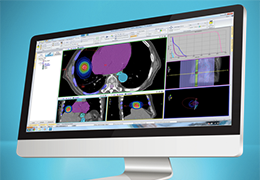

Visualization Tools

Parametric and non-parametric statistical maps may be superimposed both on the original functional scans as well as onto T1-weighted 2D or 3D anatomical reference scans. Time courses of selected regions-of-interest (ROIs) are available both in 2D and 3D representations. Statistical maps may be computed either in the 2D or 3D representation since structural as well as functional 4D data (space x time) are transformed into Talairach space. This allows you to compare activated brain regions across different experiments and across different subjects

Segmentation

Segmentation of tissue (e.g., isolating the brain, differentiating gray and white matter) is performed using region-growing methods, filter operations as well as the application of 3D templates. Using the mouse it is very easy to explore a 3D volume with superimposed pseudocolor-coded statistical maps in a four-window representation showing a sagittal, coronal, transversal and oblique section. Based on a (segmented) 3D data set a three-dimensional reconstruction of the subjects' head and brain can be calculated and displayed from any specified viewpoint using volume or surface rendering.